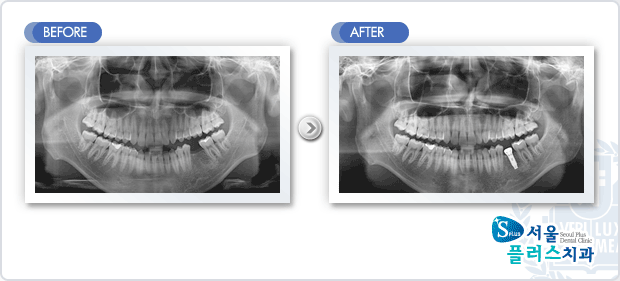

[임플란트] 임플란트 - 하악 구치부 상실부위 임플란트 식립